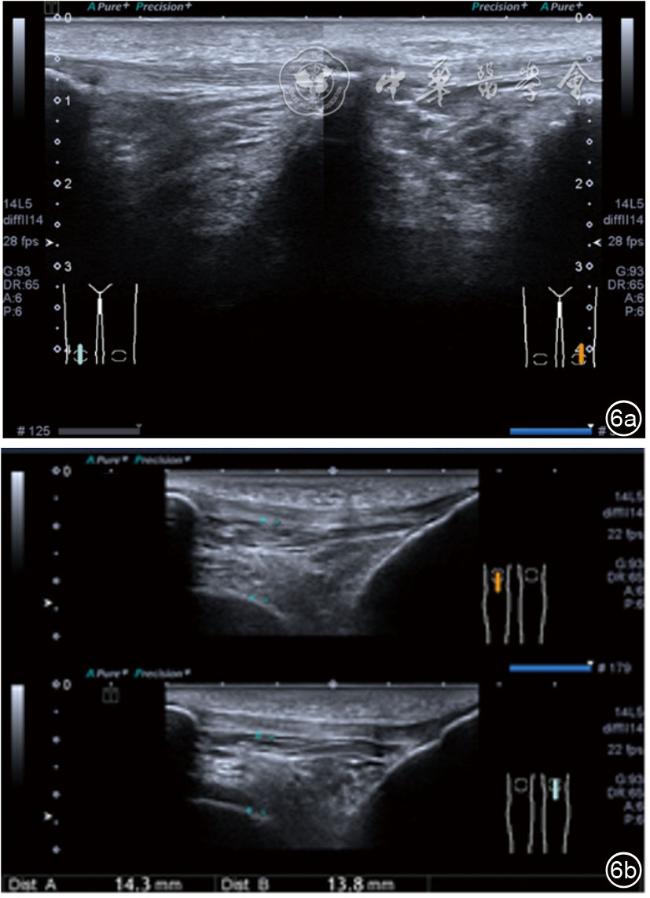

1.关节内表现。(1)骨改变。表现为骨末端或关节周缘出现的骨质局部突起改变,其后方伴或不伴有声影,多见于膝关节内侧缘和外侧缘(图1)。(2)软骨改变。股骨关节面改变可以在长轴及短轴切面显示,嘱患者屈曲膝关节,足平置于检查床,股骨滑车及股骨髁上半部分的关节面即可轻松显示。超声探查可见股骨负重面关节软骨发生不同程度的改变,轻者关节软骨浅侧边界模糊,重者可见关节软骨薄、缺失,软骨下骨缺损改变(图2)。(3)半月板外突。一般内侧半月板突出多见,外侧半月板突出比较少。半月板可见不同程度的外突,同时伴有膝内侧副韧带向外移位(图3)。半月板外周缘性滑脱是指半月板突出超出胫骨平台边缘的距离≥3 mm,其可引起一系列临床症状,早期诊断、早期治疗可以预防骨关节的进一步损伤。(4)交叉韧带损伤。可见前后交叉韧带增粗,回声减低(图4)。(5)髌上囊积液。膝关节是最容易发生积液的关节之一。患者仰卧位,关节积液最常见于膝关节上外侧,因为关节囊向髌股关节上外侧突出。髌上囊积液采用10~18 MHz的高频线阵探头于股四头肌腱纵断面及横断面扫查均可显示,探头频率取决于患者体型。超声可见低回声积液,慢性可伴有丛状滑膜增生(图5)。(6)脂肪垫水肿。脂肪垫在髌骨附着点处回声增强、增厚(图6)。

图6 脂肪垫增厚、髌腱下回声增强超声图像